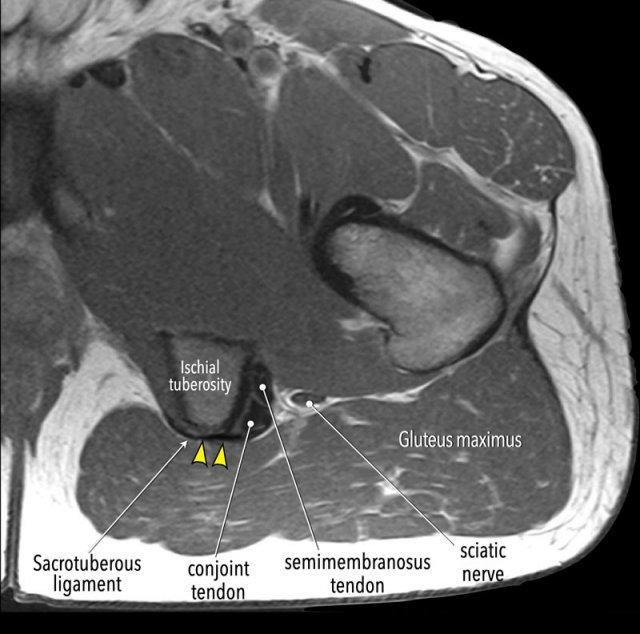

Các cơ gân kheo bám tận vào vùng trên của ụ ngồi.

Trên hình ảnh nhìn từ phía sau, có thể thấy gân cơ bán màng bám vào phía ngoài trong khi thân cơ lại nằm ở phía trong.

Gân chung của cơ nhị đầu đùi và cơ bán gân bám vào diện trong (medial facet).

Cơ nhị đầu đùi và cơ bán gân bám vào ụ ngồi thông qua gân chung, gân này có kết nối nông với dây chằng cùng-ụ ngồi (sacrotuberous ligament – STL). Khi các gân bị bật khỏi ụ ngồi nhưng kết nối với dây chằng này vẫn còn nguyên vẹn, dây chằng cùng-ụ ngồi có thể đóng vai trò như một “dây cứu sinh” giúp ngăn gân bị co rút.

Gân cơ bán màng chạy bên dưới gân chung và bám vào phía ngoài hơn trên ụ ngồi.

Lưu ý rằng gân cơ bán màng bám vào phía ngoài so với gân chung.

Dây thần kinh tọa nằm rất gần với điểm bám gân kheo gần, cách khoảng một centimet về phía ngoài.

Trên ảnh MRI mặt phẳng axial này, hãy chú ý kết nối dạng cân (aponeurotic) giữa dây chằng cùng-ụ ngồi và phần nông của gân chung.

Trong một số trường hợp, các gân có thể bị bật khỏi ụ ngồi trong khi kết nối này vẫn còn nguyên vẹn. Trong những trường hợp như vậy, sẽ không có hiện tượng co rút gân và thường không cần can thiệp phẫu thuật.